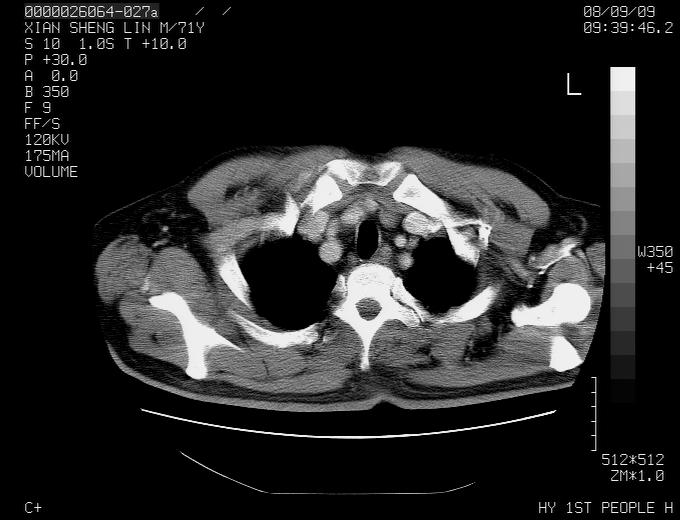

标题: CT15869:男性,71岁,因咳嗽而就诊,请讨论右上肺病变性质 [打印本页]

标题: CT15869:男性,71岁,因咳嗽而就诊,请讨论右上肺病变性质

患者,男性,71岁,因咳嗽而就诊,

典型的右肺中心性肺癌并纵隔淋巴结转移

右肺中心性肺癌并纵隔淋巴结转移可能性大!

病灶中等程度强化 还是支持肺癌诊断

考虑右肺中心性肺癌并右肺门及纵隔淋巴结转移。

1,右肺中心型ca,气管隆突旁淋巴结转移。

2,右膈明显抬高,建议肝脏扫描排除转移或原发灶。